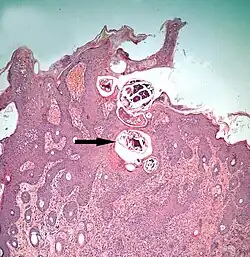

Psoroptes ovis mite infestation of skin; histological section: Mites, arrowed, shown in superficial layers of epidermis

The diagram Mite infestation sites on skin shows where typical infestations of different taxonomic groups mites on livestock animals occur on or in the host's skin.[9] The position of these mites in relation to the skin or other organs is crucial for their feeding and also for their veterinary diagnosis and options for treatment. The mites either feed on the tissues of the skin using penetrating mouthparts or on the inflammatory exudate that results from the action of the mouthparts and saliva of the mites on the skin.[12] Demodectic mites have mouthparts adapted to penetrate and suck out the contents of individual cells of hair follicles.[13] It is usual for all active stages of the mite lifecycle to feed as parasites, but the trombiculid mites are an exception. Most of the parasitic mites do not feed directly on blood, but the dermanyssid mites and larval trombiculid mites directly suck up capillary blood as their exclusive food. The tube through which food is ingested and saliva excreted during feeding is formed in most mites by apposing the sheath that contains the chelicerae against the hypostome. However, the trombiculids are an exception. Some species of mites (Analgidae) have adapted to feeding on keratin and skin debris amongst the feathers of birds, and other species have adapted to feed directly on internal tissues such as air-sacs or lungs (Cytoditidae and Laminosioptidae). Psoroptic mites feed superficially at the stratum corneum; the photograph of a histological section of skin infested with Psoroptes ovis, and the photograph of the surface of a host's skin infested with P. ovis looking like white dots, show this type of feeding. Sarcoptic mites feed by burrowing within the living layers of the epidermis, mainly stratum spinosum. Demodectic mites feed in a position technically external to the skin, between the epidermis and the hair shaft in hair follicles. Dermanyssid and trombiculid mites feed whilst external to the skin by piercing the skin with, respectively, their chelicerae or a stylostome feeding tube. Mites at other sites feed by using their chelicerae to scrape either at the skin surface, or at base of feather, or to penetrate and scrape at internal tissue such as air-sac or lung.

Section through skin infested with Demodex in the hair follicles (arrowed), which are surrounded by infiltration of inflammatory cells

Demodecosis in cattle caused by Demodex bovis can occur as dense, localized infestations with inflammation of the epidermis in hair follicles.[36] This leads to pustular folliculitis and indurated (thickened) plaques within the skin. On cattle, these localized foci of infestation can become so large as to be clearly visible externally. The value of the hides from cattle infested this way is reduced.[37] Pigs may be similarly affected by infestations with Demodex.[38]